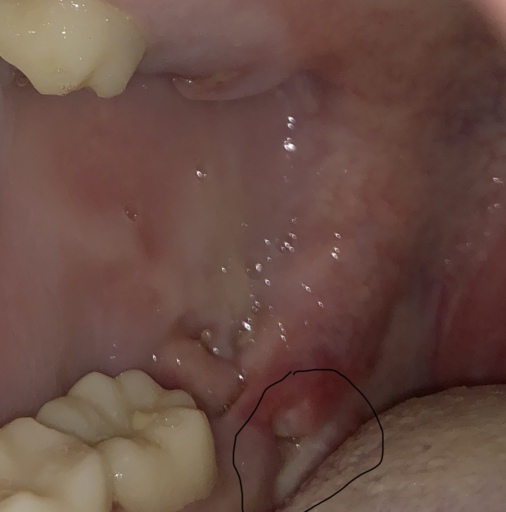

Do I need a biopsy? Is this a mucucele?

See pics please. This is soft to the touch. Been there a few years. I thought is was a blocked saliva duct but now it has the dark area beneath it which is new. Of note. About 6 years ago a general dentist said to keep an eye on it for any changes. He said it was most likely a mucocele (sp?) Again, it is soft to the touch.

See pics please. This is soft to the touch. Been there a few years. I thought is was a blocked saliva duct but now it has the dark area beneath it which is new. Of note. About 6 years ago a general dentist said to keep an eye on it for any...